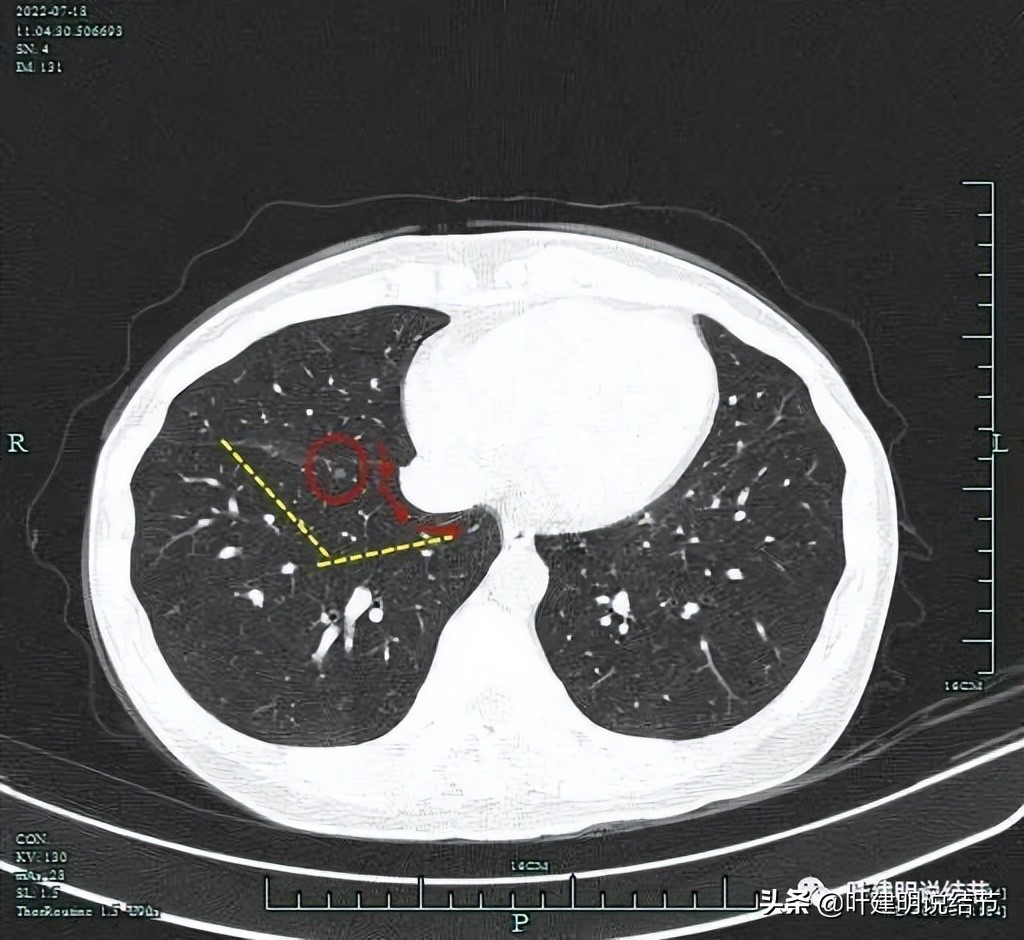

如果不定位,直接做前与内基底段切除,至少要虚线所示区域的范围,下叶损失较多。而如果定位后楔形切除,则如下所示:

如果从肺表面进针,不管上图的那个方向进,都位置很深,而且用钩针定位的话,只能看见入针处,钩在哪里并不一定容易看到,位置还是要估计,并不准确。我在想,能不能用钩针或医用胶直接从前胸壁穿过中叶钩在病灶处?如下图所示的路径:

这样的距离会短一点,针道这么细过中叶影响也不大,而且能垂直于病灶处,位置更准确,切除范围也比较小。